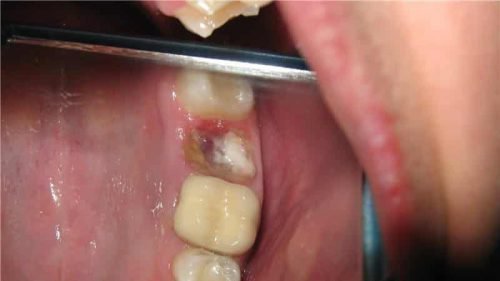

Нагноение лунки из-за альвеолита

- Осколок зуба. При некачественно проведенной процедуре удаления в десне может остаться осколок, провоцирующий воспаление десны. Появляется отек раны, следом усиливаются болевые ощущения. Запах изо рта по этой причине часто возникает после удаления зуба мудрости, так как его положение (горизонтальное, с наклоном) и удаленность от центра затрудняют проведение врачебных манипуляций. Кроме того, зуб мудрости может быть ретенированным, не прорезавшимся. В этом случае риск оставить осколок в десне очень высок.

- Частичка зуба, оставленная стоматологом в ране, становится причиной боли и зловония. Если остался осколок, десна опухает, боль усиливается. Нередко подобная ситуация возникает при экстракции зуба мудрости из-за его сложного расположения в ротовой полости.

При удалении старых зубов часто образуются сколы. При этом может отколоться как часть верхушки, корня или эмали. Небольшой осколок часто остаётся незамеченным и становится причиной плохого заживления десны. Если был вырван моляр сверху, такие сколы выходят в течение нескольких дней самостоятельно. Если же удалили зуб снизу, выход осколков затруднён. Они остаются в лунке и не дают ранке затянуться.

Если к незаживающей ранке присоединилась инфекция, формируется гнойный воспалительный процесс и появляется галитоз.